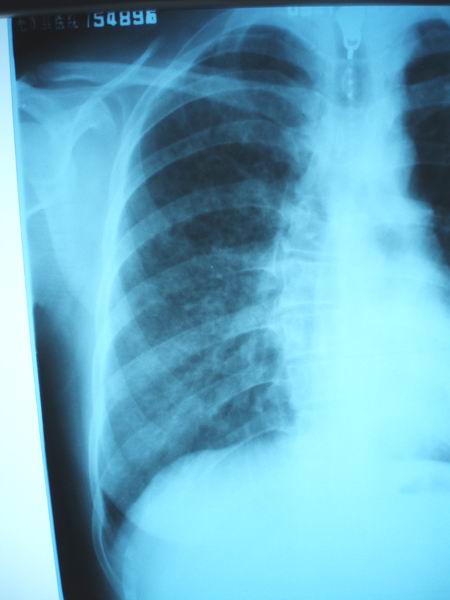

病人36岁,女、5年前就有过一次咳嗽发烧,当时也没诊断清,市级医院说是支气管肺炎,后来消炎加抗痨治疗了4个月就好了。这次病人主要是胸闷,晚上有点低烧3天,咳血痰,请各位老师帮忙看看诊断什么病

图像不清楚,两肺下野参出性病变。

胸椎右弯!图像不清楚,两肺下野参出性病变。

1)右肺感染性病变;建议抗炎治疗后复查,必要时行ct扫描检查。2)脊柱胸段右突侧弯。

右肺感染性病变,脊柱胸段右侧弯曲畸形

右肺条片影,考虑右下肺炎性改变。

右肺感染性病变;建议抗炎治疗后复查,必要时行ct扫描检查。脊柱胸段右突侧弯。

)右肺感染性病变,考虑右肺下野支气管扩张,建议抗炎治疗后复查,必要时行ct扫描检查